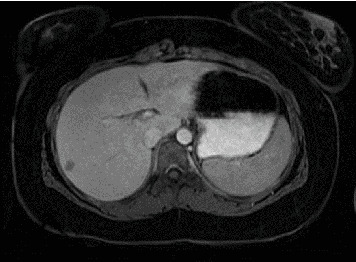

Abstract Image

Solid pseudopapillary neoplasms (SPNs) represent a tumor of the exocrine pancreas, belonging to the group of pancreatic cystic neoplasms. It is exceedingly uncommon for SPNs to manifest in extrapancreatic locations, such as the mesocolon, greater omentum, jejunum, and ovary. SPNs are considered very rare, constituting about 0.17%-2.5% of all pancreatic neoplasms and 6% of cystic pancreatic neoplasms. We present two pediatric cases of SPNs: one involving a 16-year-old female patient and the other a 14-year-old girl, both diagnosed and treated in our center with surgical resection. The experience of our center confirms that wide margin surgery, with associated metastasectomy if necessary, represents the therapy of choice for SPNs, ensuring effective control of the disease.